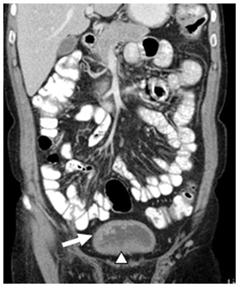

A 60 year old male was referred to us for complaints of intermittent painless gross haematuria since 18 months associated with passage of blood clots of variable size. Physical examination was within normal limits and past medical history was non contributory. Haematological and coagulation parameters were within normal limits. Urine analysis showed several WBCs, RBCs with mild albuminuria. The CECT scan of abdomen and pelvis revealed mild right hydronephrosis and an irregular UB wall thickening with few polypoidal growths along its right supero-lateral aspect (Figure 1). On cystoscopy, few papillary growths were observed, largest being 2cm, at right lateral wall involving the right ureteric orifice. Rest of the bladder mucosa appeared irregular, thickened and edematous. The growth was resected transurethral and random biopsies were taken. Histopathology of the resected tissue revealed abundant deposition of acellular, eosinophlic material beneath the epithelial lining with large amount being deposited in the vessels wall with no tumour cells. Congo red staining and apple-green birefringence in polarized light confirmed the diagnosis of amyloidosis (Figure 2A, 2B). Post-operative recovery remained uneventful and the patient was asymptomatic with no recurrence in bladder on repeated cystoscopy after two year of follow up.

Figure 1 CECT Showing Bladder Wall Thickening At Base (Arrow Head) And Polypoidal Growths At Right Lateral Wall (Arrow).